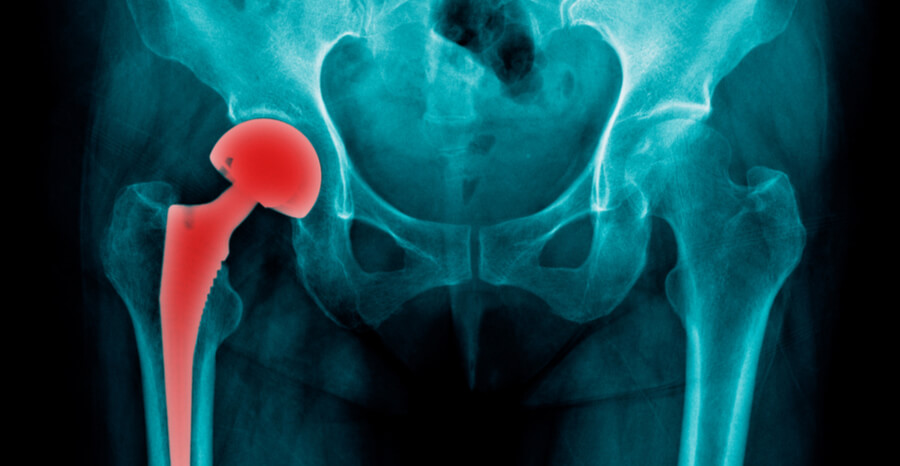

Total Hip Replacement (THR) procedure replaces all or part of the hip joint with an artificial device (prosthesis) with a plastic liner in between to restore joint movement

The surgery varies from a simple liner exchange to changing one or all of the components. Extra bone (cadaver bone) may need to be used to make up for any bone loss.